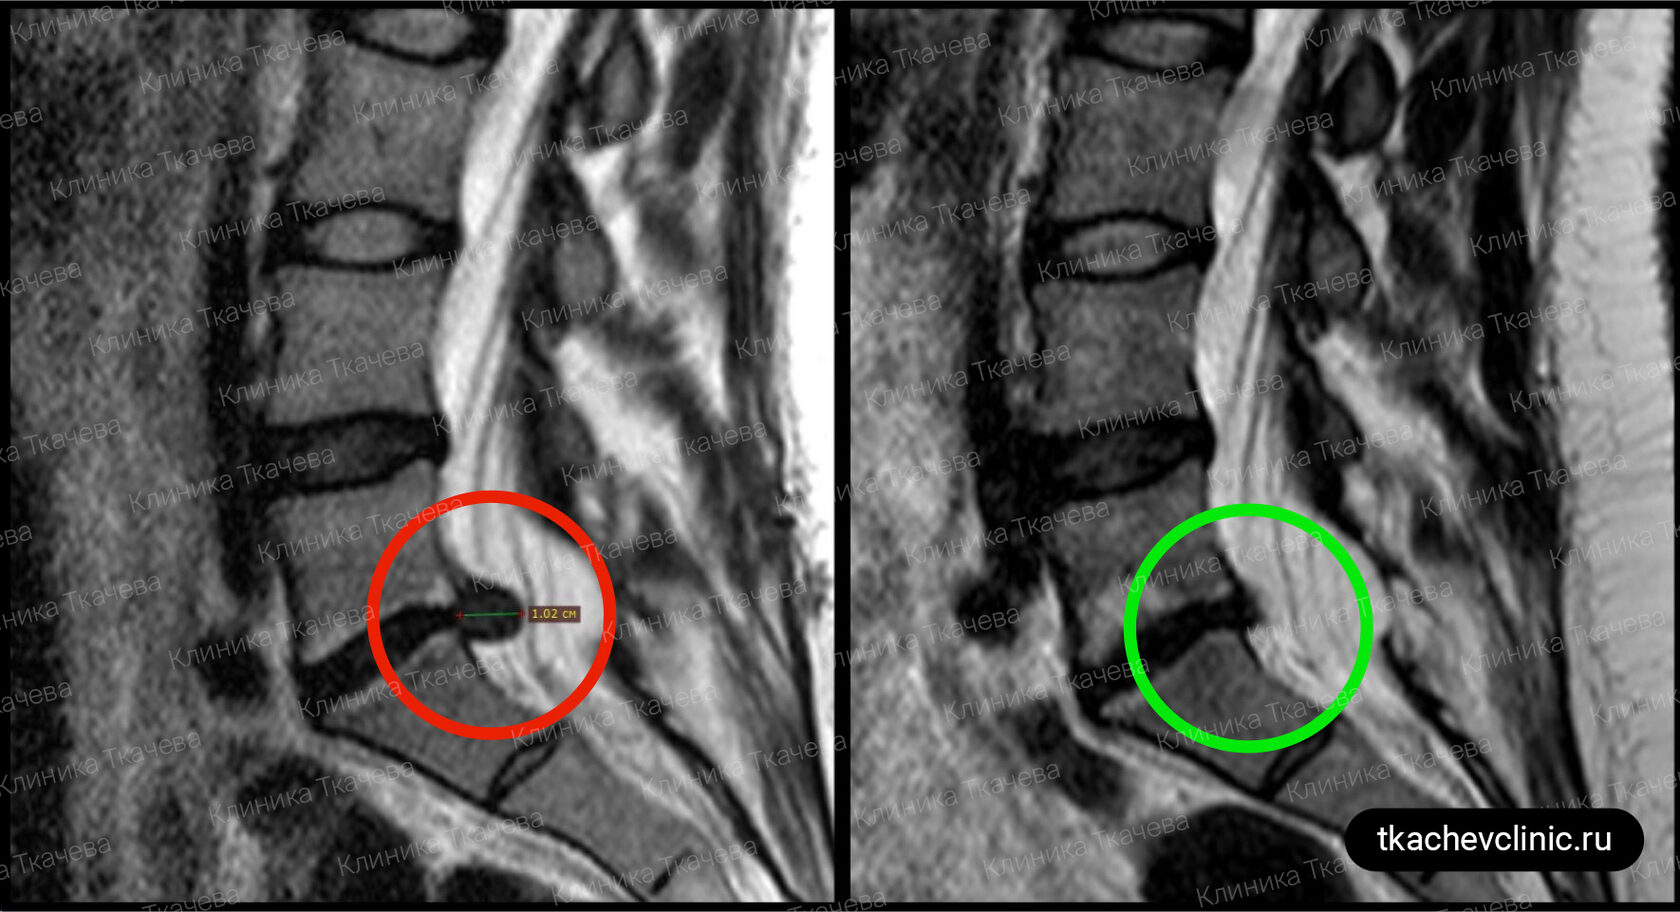

Латерализация грыжи